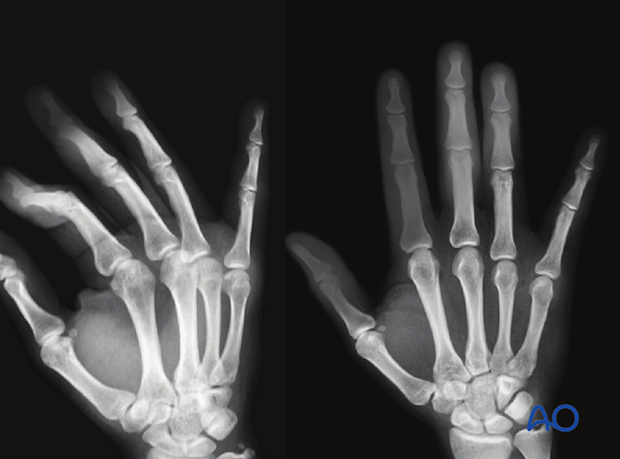

This oblique and AP x-ray show a lateral dislocation of the PIP joint of the 3rd finger.